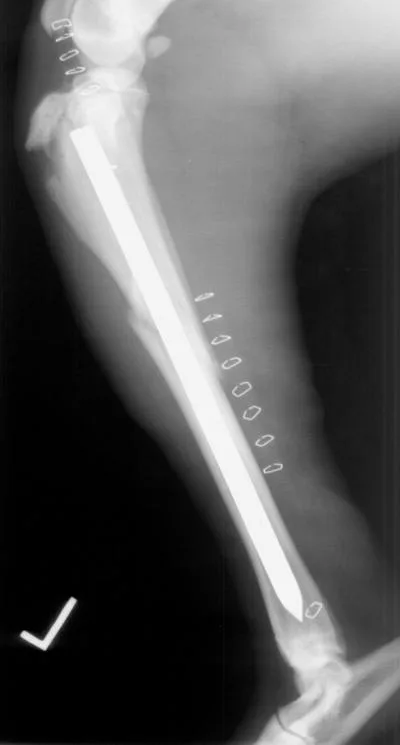

The interlocking-nail system (Innovative Animal Products, Rochester, MN) is another effective implant system for biologic management of comminuted fractures in dogs and cats.1 The interlocking nail is a modified Steinmann pin having transverse holes designed to accommodate screws or bolts. The addition of screws or bolts increases the ability of the pin to resist rotational and compressive forces at the fracture site (Figures 2A, B). This type of fixation is commonly used for stabilization of fractures of the femur and tibia in humans.

Interlocking nails are used in dogs and cats for repair of fractures of the humerus, femur, and tibia. The interlocking-nail system is less expensive than a bone-plate system but has similar biomechanical properties.8 Interlocking nails are easy to apply and are a good option for general practitioners who do not want to invest in a bone-plate system.

Fractures managed using interlocking nails and biologic technique develop extensive bridging callus and early return to function. A minimally invasive surgical approach (note the surgical skin staples) was made to this fracture to minimize disruption of the blood supply to the bone fragment. The fracture fragments quickly become incorporated in the callus if soft tissue attachments can be maintained.

Healing of the comminuted tibial fracture shown in Figures 2A and 2B after stabilization using an interlocking nail system. This fracture reached bony union in 8 weeks.